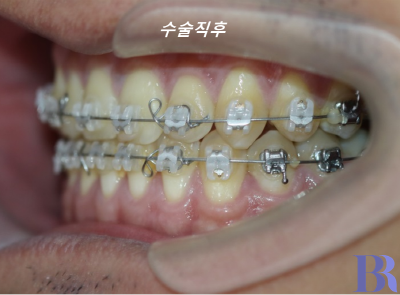

1년정도의 술전교정을 마친 후

수술직후 모습입니다.

수술 직후 치아 모습입니다

반대교합이 잘 해소가 되었네요

교합도 안정적으로 맞물립니다.

교합도 아주 긴밀하게

수술이 잘되었습니다